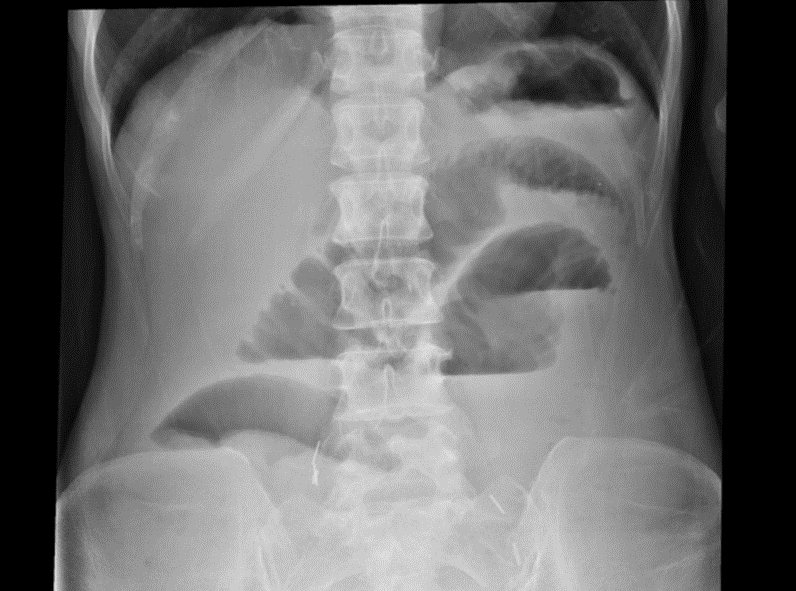

突然ですが、レントゲンクイズを出題します。画像の所見を読んで、離床のリスクと注意点を説明してください。

[クイズ解答例]

細かいひだの小腸ガスの貯留と、小腸の拡張がみられ、腸閉塞が疑われるため、離床は立ち止まり腸閉塞に対する治療・コントロールを優先すべきと考えられます。